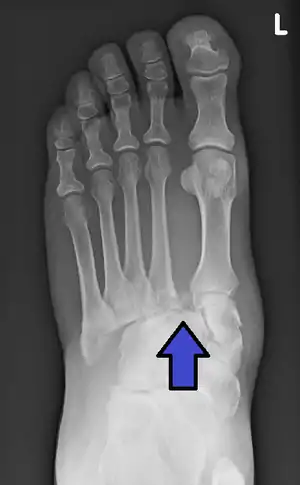

![]() | |

| An X-ray of a Lisfranc injury | |

In a high energy injury to the midfoot, such as a fall from a height or a motor vehicle accident, the diagnosis of a Lisfranc injury should, in theory at least, pose less of a challenge. There will be deformity of the midfoot and X-ray abnormalities should be obvious. Further, the nature of the injury will create heightened clinical suspicion and there may even be disruption of the overlying skin and compromise of the blood supply. Typical X-ray findings would include a gap between the base of the first and second toes.[8] The diagnosis becomes more challenging in the case of low energy incidents, such as might occur with a twisting injury on the racquetball court, or when an American Football lineman is forced back upon a foot that is already in a fully plantar flexed position. Then, there may only be complaint of inability to bear weight and some mild swelling of the forefoot or midfoot. Bruising of the arch has been described as diagnostic in these circumstances but may well be absent.[9] Typically, conventional radiography of the foot is utilized with standard non-weight bearing views, supplemented by weight bearing views which may demonstrate widening of the interval between the first and second toes, if the initial views fail to show abnormality. Unfortunately, radiographs in such circumstances have a sensitivity of 50% when non-weight bearing and 85% when weight bearing, meaning that they will appear normal in 15% of cases where a Lisfranc injury actually exists.[10] In the case of apparently normal x-rays, if clinical suspicion remains, advanced imaging such as magnetic resonance imaging (MRI) or computed tomography (CT scan) is a logical next step.[11]